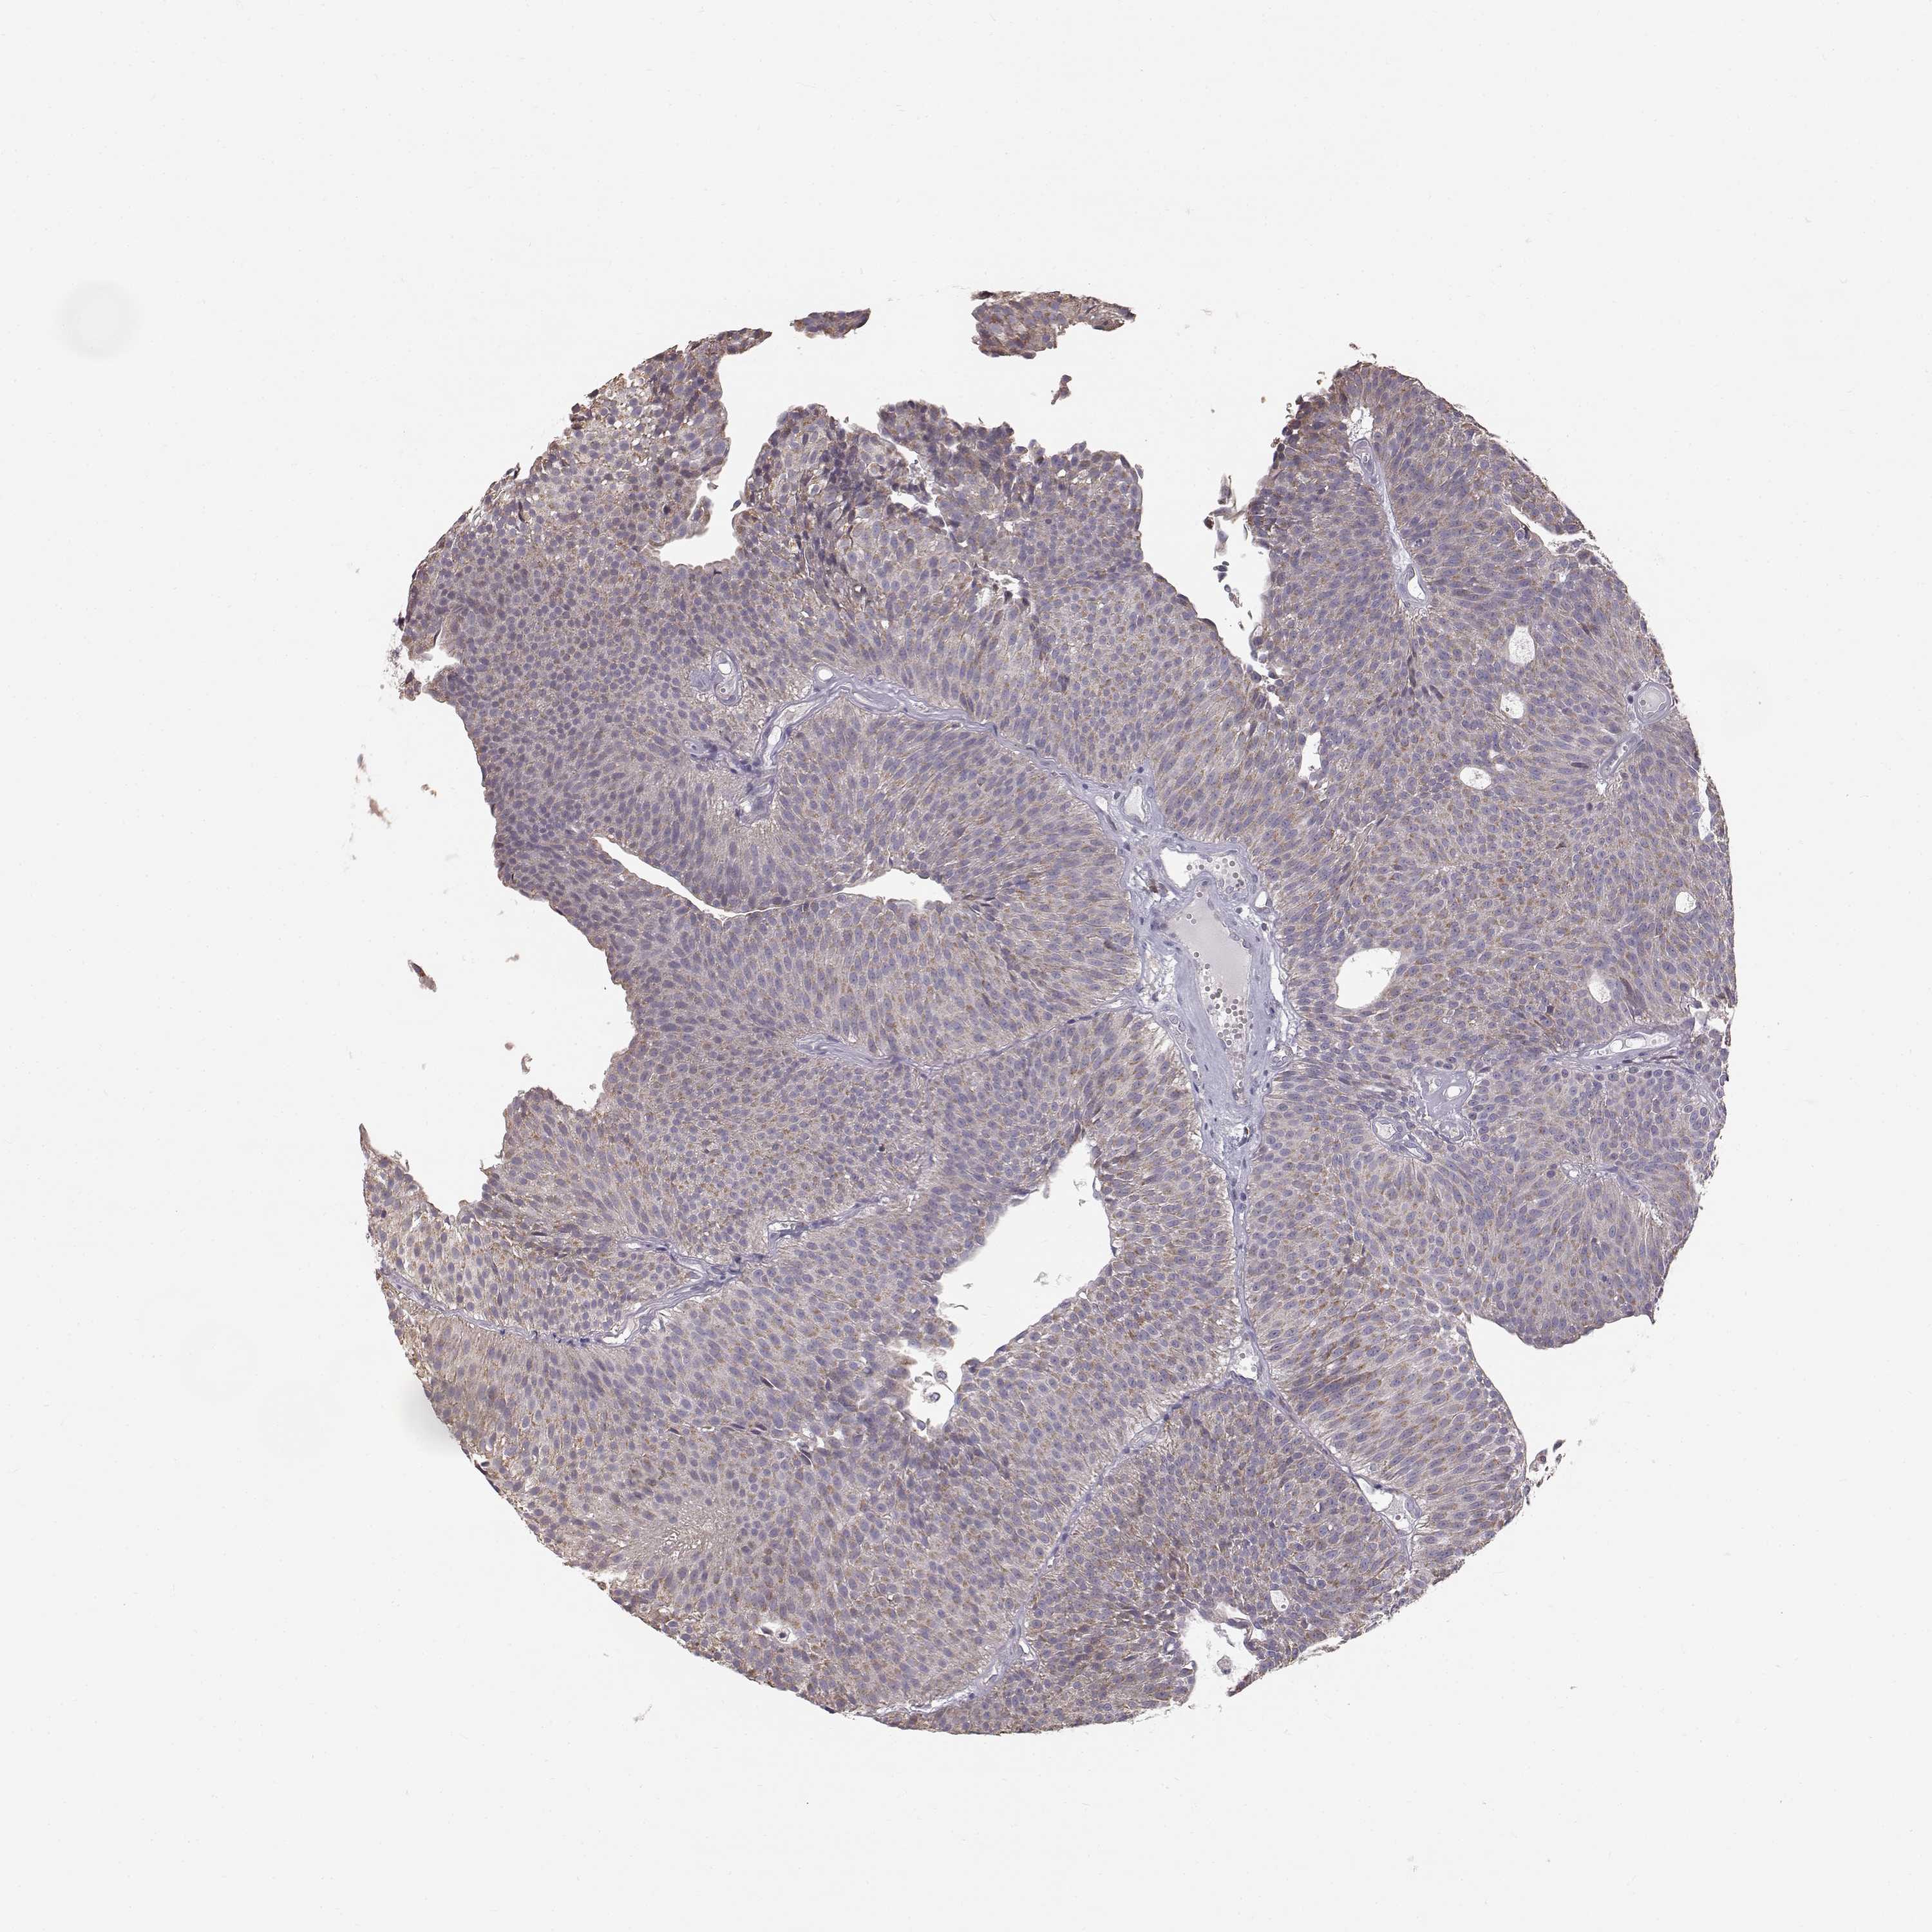

UROTHELIAL CANCER - Protein expressioni

A mouse-over function shows sample information and annotation data. Click on an image to view it in a full screen mode. Samples can be filtered based on level of antibody staining by selecting one or several of the following categories: high, medium, low and not detected. The assay and annotation is described here.

Antibody stainingi

Antibody staining in the annotated cell types in the current human tissue is reported as not detected, low, medium, or high, based on conventional immunohistochemistry profiling in selected tissues. This score is based on the combination of the staining intensity and fraction of stained cells.

Each image is clickable and will lead to virtual microscopy that enables deeper exploration of all samples and also displays staining intensity scores, fraction scores and subcellular localization as well as patient and tissue information for each sample.

Antibody HPA005788

Antibody CAB022073

Staining

High

Medium

Low

Not detected

Intensity

Strong

Moderate

Weak

Negative

Quantity

>75%

75%-25%

<25%

None

Location

Nuclear

Cytoplasmic/membranous

Cytoplasmic/membranous,nuclear

Urothelial carcinoma, Low grade